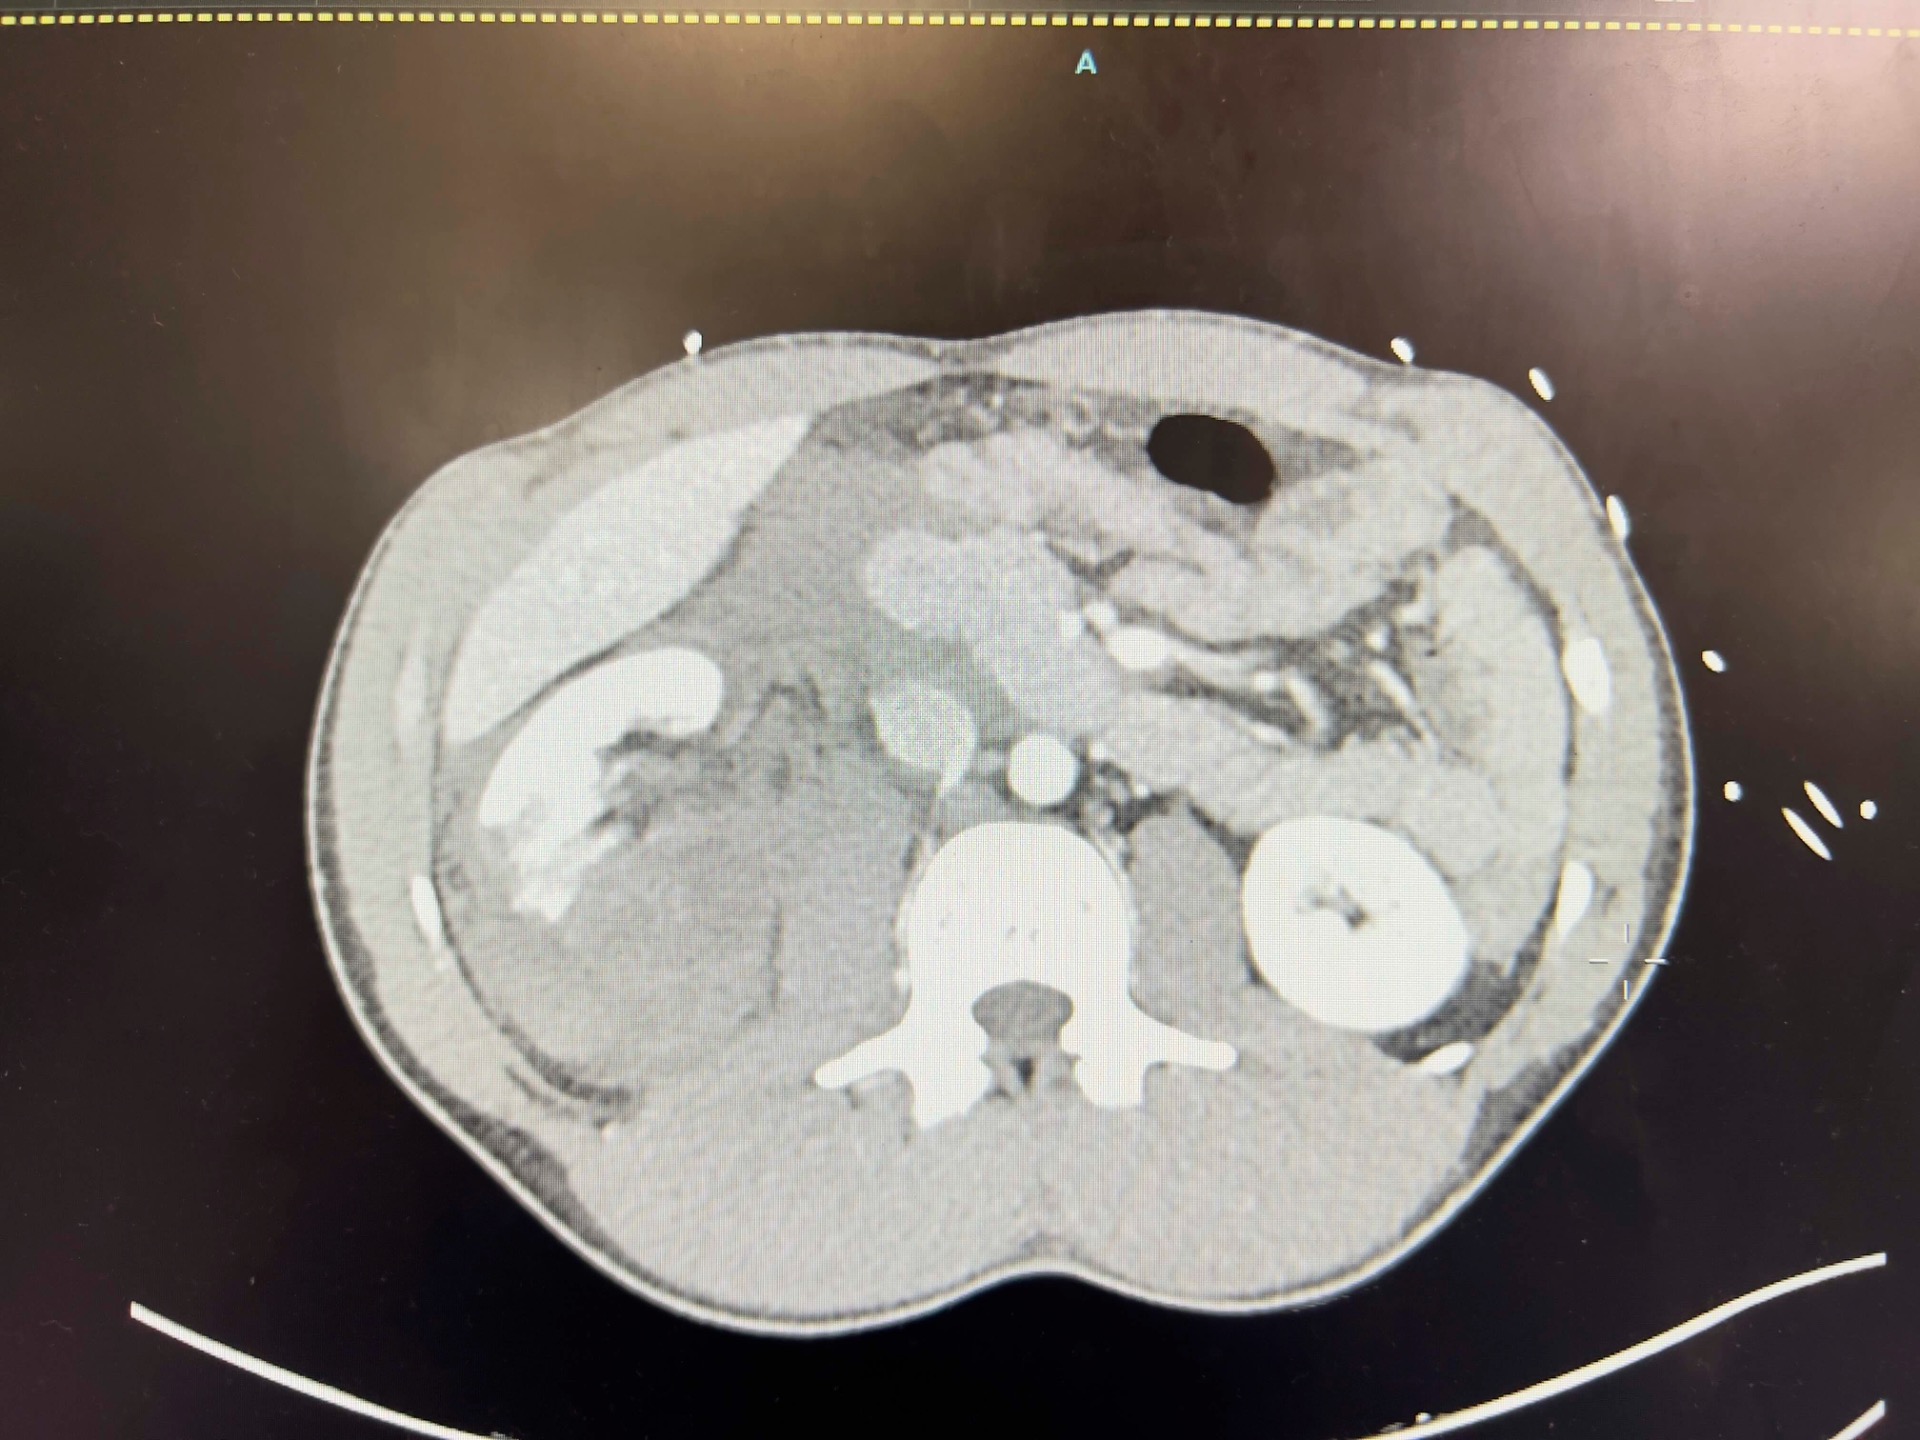

This is his CT:

In the patient's scan, the upper pole of the R kidney, the parenchyma is hyperechoic and heterogenous. The upper pole is enlarged and the normally regular contour of Gerota's fascia is disrupted. It is difficult to see if there is anechoic free fluid in the cine loop. However on CT there is a fair bit of FF around the liver. This may have been visualised by imaging the paracolic gutter (location most sensitive for FF in trauma).